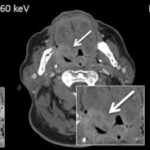

Dual-energy is constantly gaining ground. This is also the case for head and neck imaging. This study may well encourage us to change our protocols. Article: Comparison of dual- and single-source dual-energy CT in head and neck imaging Authors: Matthias Stefan May,...